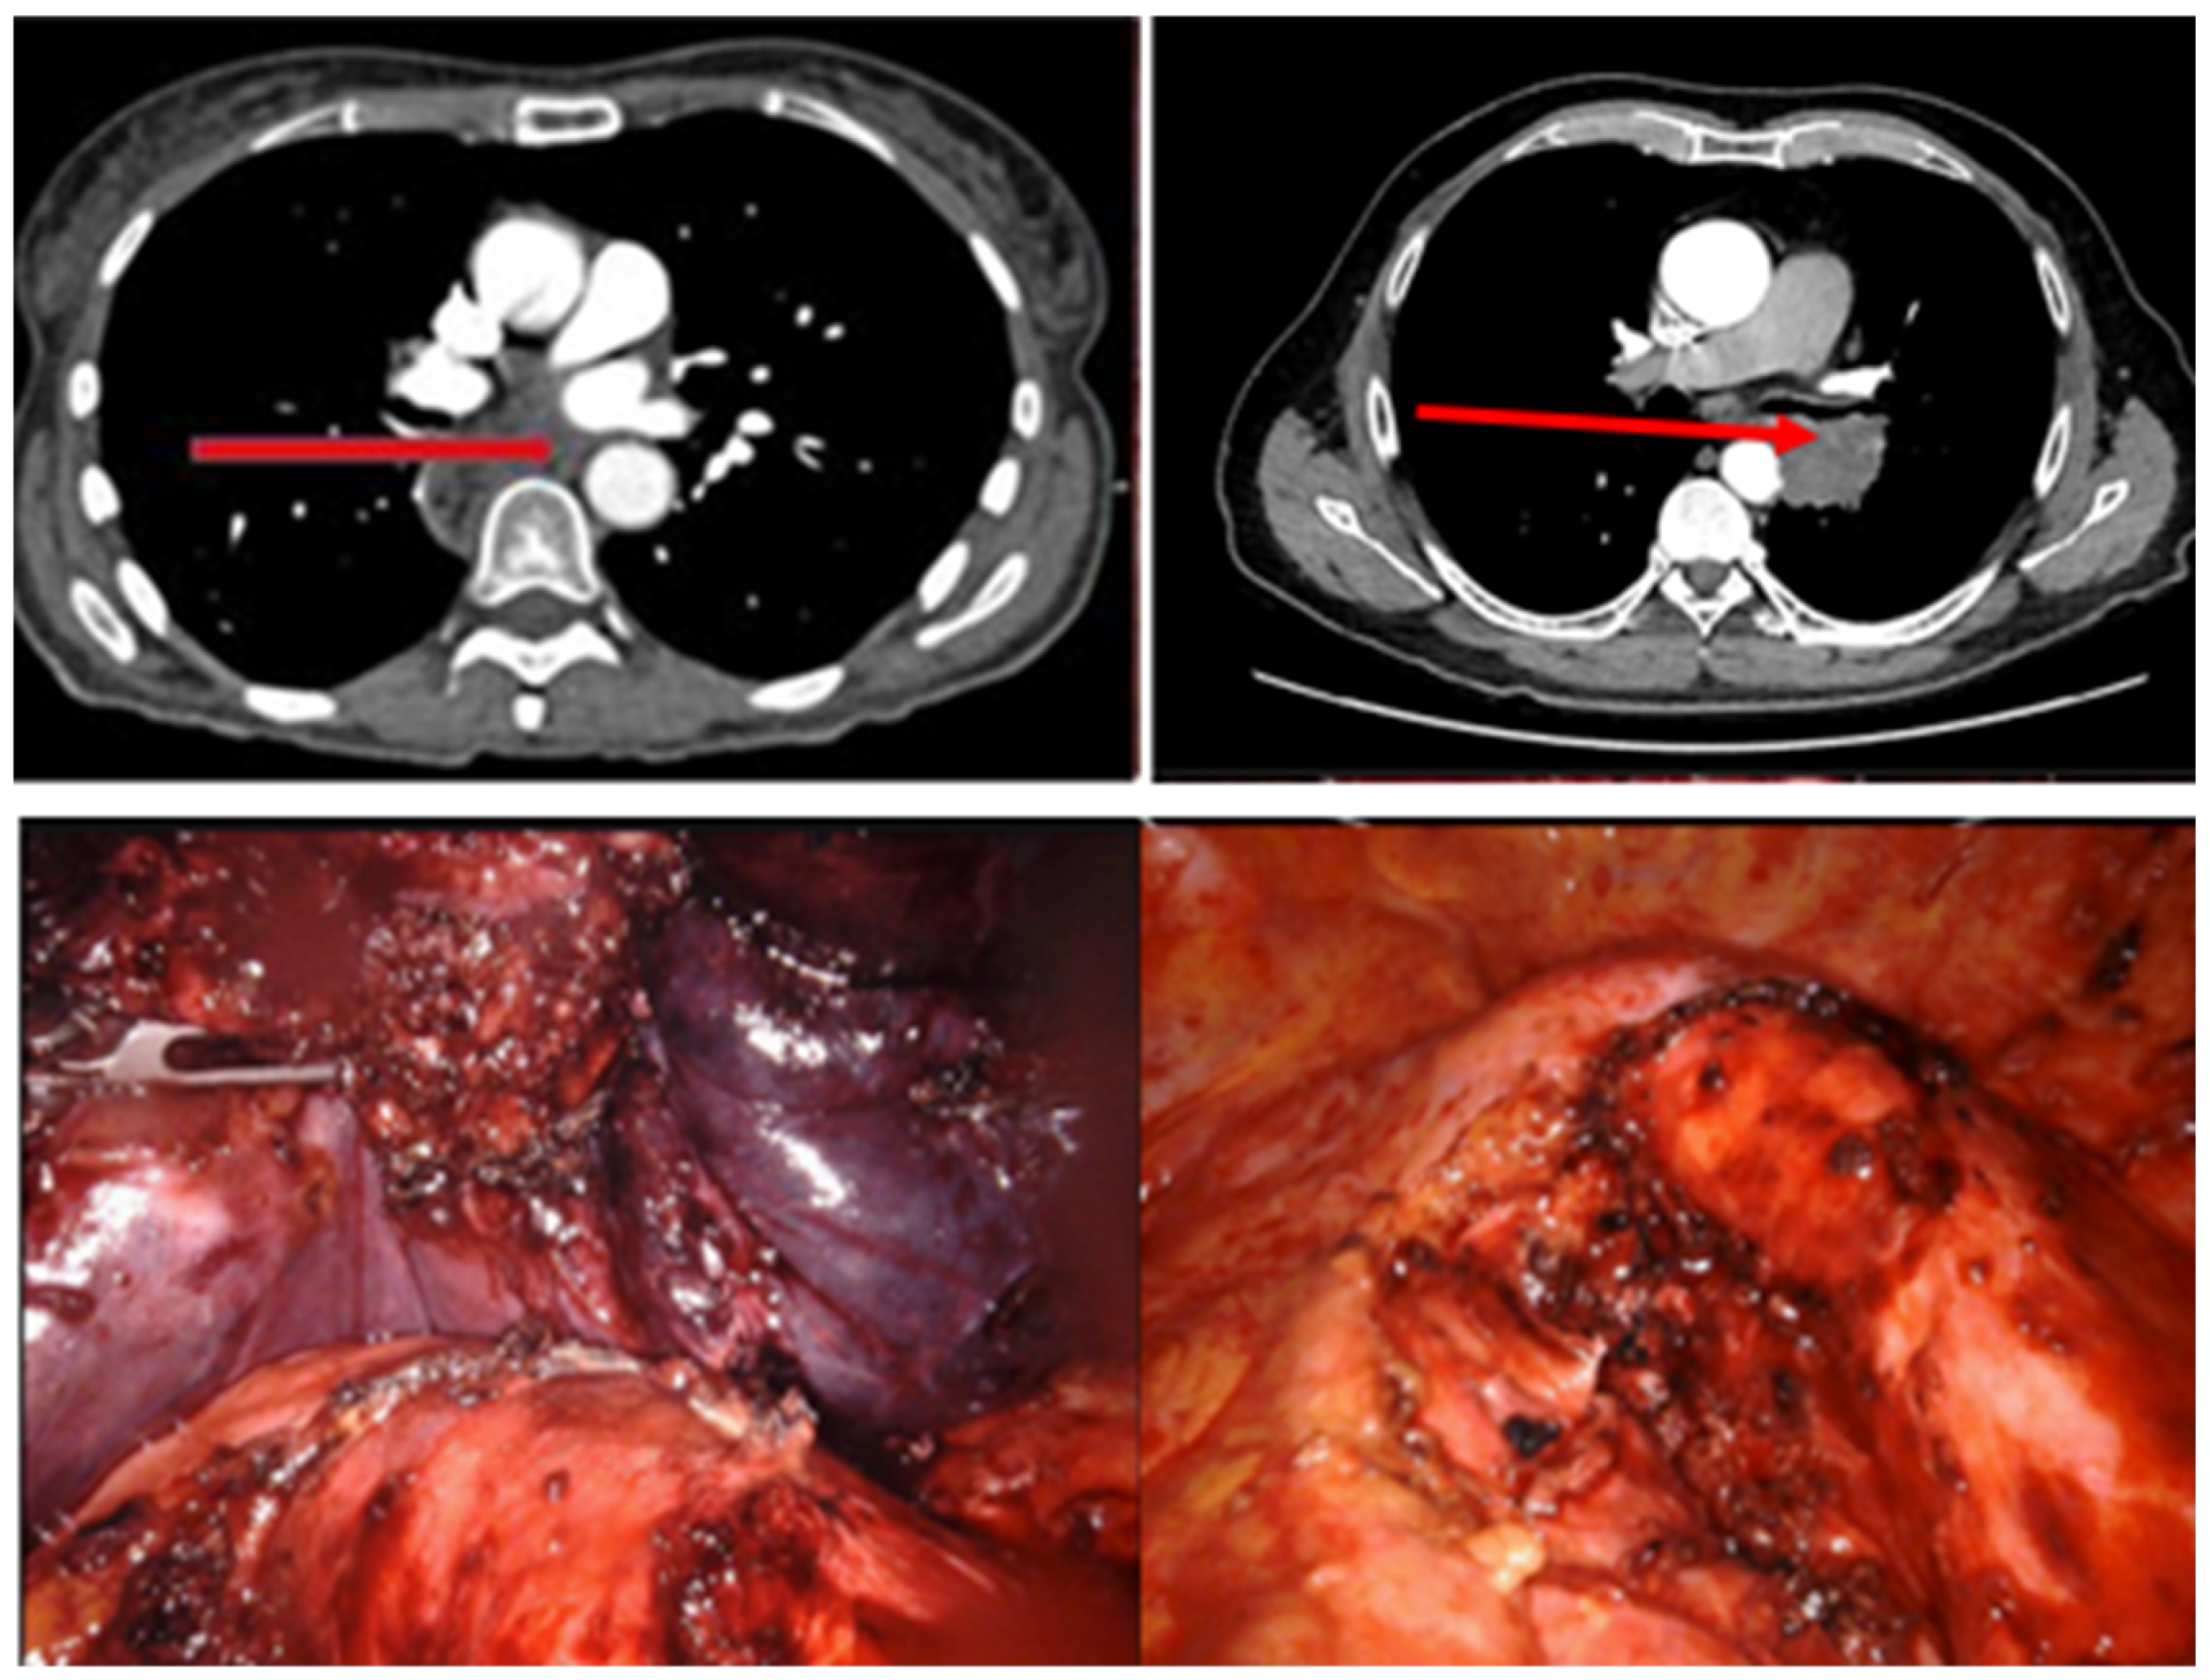

No postoperative endograft-related morbidity was recorded, specifically, no spinal cord ischemia, stroke, postoperative bleeding, access site complications, dissection, or aortic rupture (Table 4). R0 resection was achieved in seven patients. In eight patients, aortic wall infiltration was confirmed intraoperatively, and a partial, non-circumferential resection of the aortic wall was necessary, resulting in R0 not being achieved in all cases (Table 4 and Figure 1).

Figure 1.

Top: Preoperative CT scan with the tumor mass in the posterior mediastinum with suspected aortic wall infiltration. Bottom: Intraoperative view of the partially resected tumor, including aortic wall.